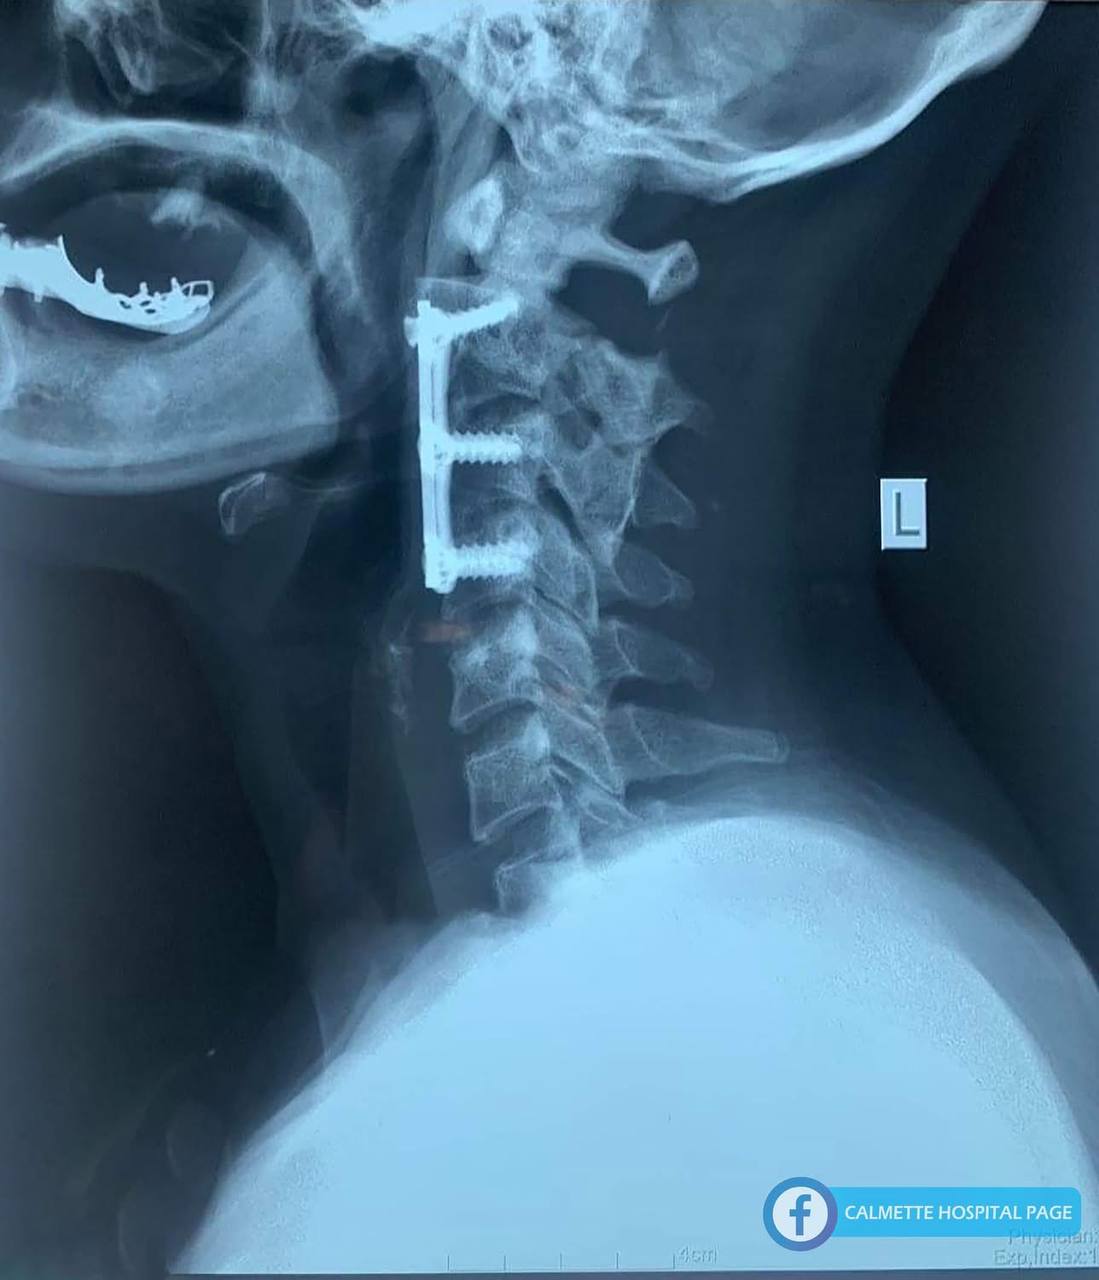

ភ្នំពេញ ៖ ការវះកាត់ចាប់ដែកអបឆ្អឹងកងកដែលបាក់ក្រោយការប៉ះទង្គិ ជាបច្ចេកទេសដែលកំពុងអនុវត្តជាសកលក្នុងការវះកាត់តំរង់ឆ្អឹងកងកដែលរំកិល រឺភ្លាត់ខុសកន្លែងអោយស្ថិតមកនៅកន្លែងធម្មតាវិញ ក្នុងគោលបំណងអោយខួរឆ្អឹងខ្នងមិនមានការគាបសង្កត់ និងកុំអោយខួរឆ្អឹងខ្នងខូចខាតបន្ថែមទៀតក្រោយការប៉ះទង្គិច។

– ថតកាំរស្មីអ៊ិច

– ថត ស៊ីធីស្កែន រឺថត អឹមអអាយ

– ចំពោះអ្នកជំងឺដែលមានការរំកិល រឺភ្លាត់ឆ្អឹង រឺក៏ឆ្អឹងកងកមិនមានលំនឹងក្រោយការប៉ះទង្កិច អ្នកជំងឺគឺតំរូវអោយមានការព្យាបាលដោយការវះកាត់អបដែកឆ្អឹងកងកខាងមុខ ដើម្បីធានាមិនអោយមានការគៀបសង្កត់ទៅលើខួរឆ្អឹងកងក។